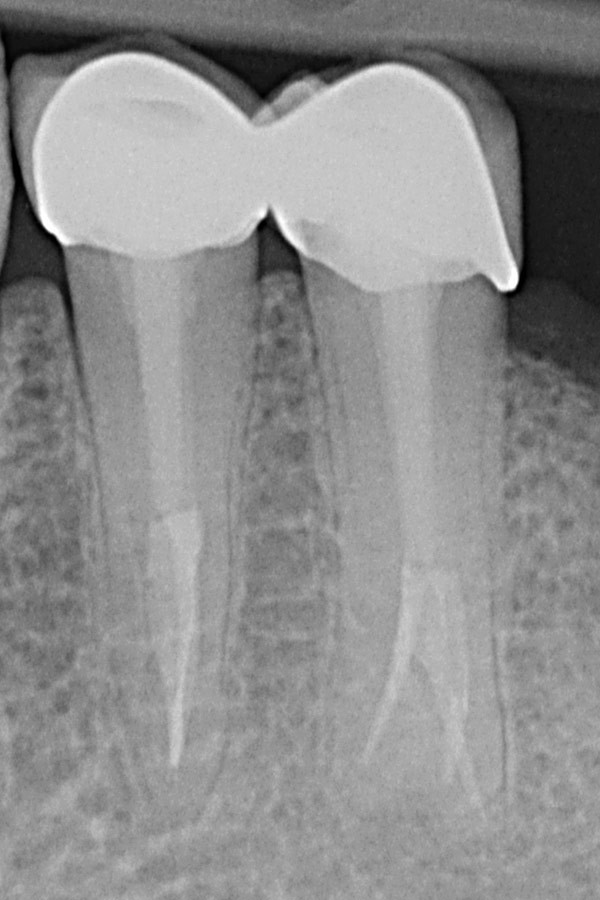

Wurzelkanalanatomie eines

zweiten Unterkiefermolaren

Bildquelle: Dr. Marco Versiani - www.rootcanalanatomy.com